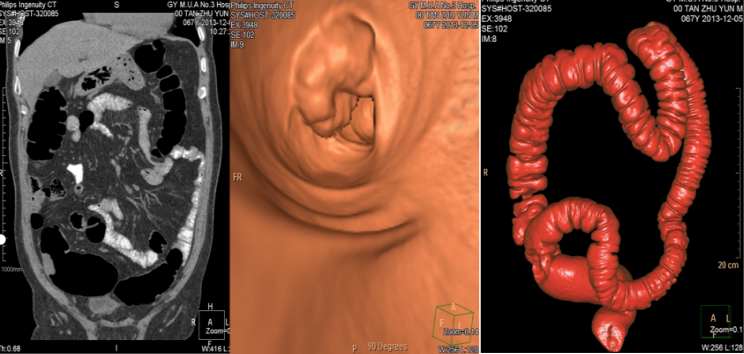

对无法做胃镜、肠镜检查的患者,可提供无创的肠道仿真内窥镜CT检查。

图为 CT仿真内窥镜检查案例

显示乙状结肠壁内有肿块形成,为早治疗提供影像基础